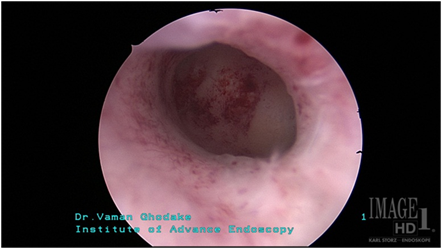

3.गर्भाशय छोटे असणे

यामध्ये गर्भाशयाची पोकळी ही छोटी असते.ही पोकळी दुर्बिणीद्वारे ऑपरेशन करुन मोठी करण्यात येते.ह्या ऑपरेशनला ‘Metroplasty’ म्हणतात. घोडके हॉस्पिटलमध्ये Metroplasty शस्त्रक्रिया दुर्बिणीद्वारेच केली जाते.अशा प्रकारच्या ऑपरेशननंतर पेशंटना गर्भधारणा होण्यास मदत झाली आहे.

1img

ऑपरेशनपूर्वी

2img

ऑपरेशनंतर